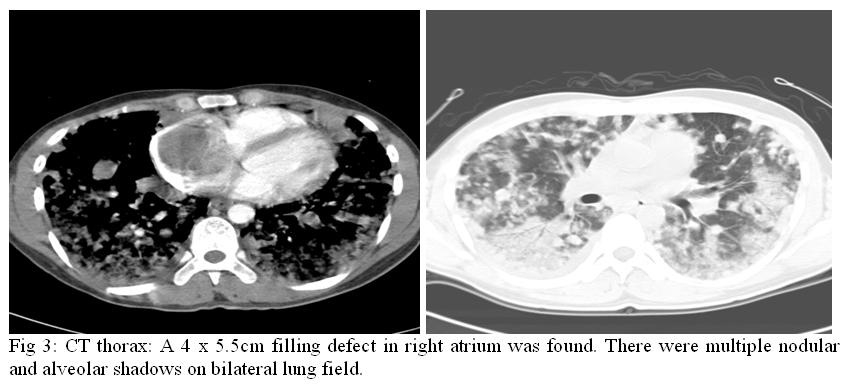

Six days after admission, he still complained of mild haemoptysis. Fever kicked up to 38.5ºc. He developed type I respiratory failure and required 50% of oxygen supplement. Haemoglobin level dropped to 7.7g/dL. CXR was repeated and showed increasing alveolar and nodular shadows(Fig.2). Computerized tomography for thorax with contrast was arranged which found a 4 x 5.5 cm filling defect in right atrium (Fig 3).

Concerning the imaging modalities, chest radiograph is useful in identifying the metastatic lung lesions. The features include multiple nodules, linear infiltrations, pleural effusion, diffuse alveolar shadow or pneumothorax.5 Contrast CT scan of thorax can identify the intracardial filling defect which has low attenuation. The metastatic lung lesions can be either nodular or cystic.6 Two dimensional echocardiogram and MRI scan offer no more specific findings. Confirmatory diagnosis still relies on tissue biopsy.